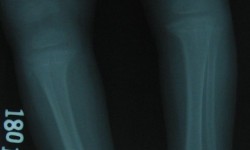

CHONDR ECTODERMAL DYSPLASIA (Ellis-Vancreveld syndrome)

By Admin | September 25, 2013 - 5:31 am | Musculoskeletal, Skeletal Dysplasias

Fig.1